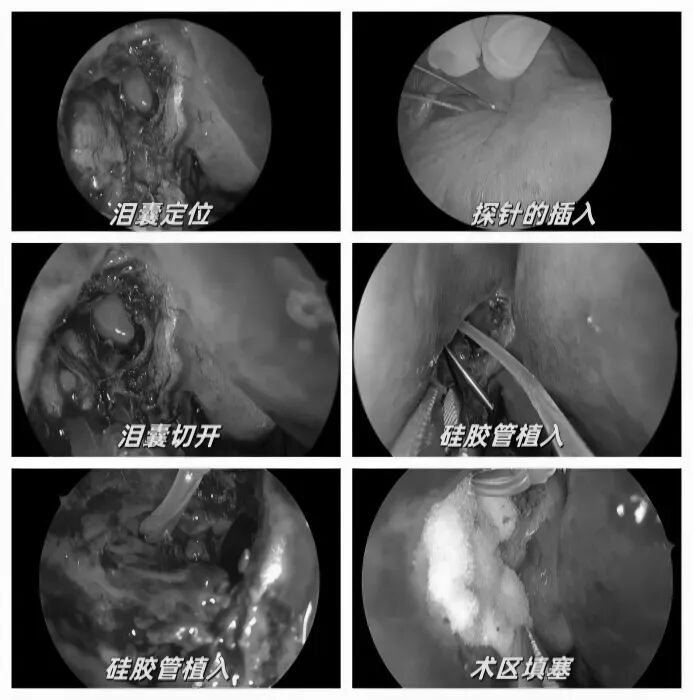

耳朵反复流脓、听力下降还有异味?当心,这可能是慢性化脓性中耳炎的症状。由于早期症状时好时坏,很多人觉得不是大问题,但拖延不治可能对听力造成不可逆的损伤。今天我们就来认清它的真面目,学会如何科学应对。 什么是“慢性化脓性中耳炎”? 慢性化脓性中耳炎,俗称“灌耳心”,典型症状包括耳内反复流脓(常为脓性分泌物,严重时可伴有臭味)、听力下降以及耳鸣等,部分患者还可能伴有眩晕。很多人是从小时候就开始出现症状,尤其是耳朵进水后容易急性发作或加重,成年后,听力持续减退往往成为主要困扰。 如果不及时治疗,炎症可能“向上”蔓延到颅内,引发脑膜炎、脑脓肿等危及生命的严重并发症。也可能侵犯面部神经或平衡器官,导致面瘫、持续眩晕或平衡障碍。最直接的后果是听力会不可逆地下降,严重时可能导致完全失聪。 “慢性化脓性中耳炎” 如何治疗? 慢性化脓性中耳炎的基础治疗需先用双氧水或生理盐水清洗耳道脓液,再滴入敏感抗生素耳液(如氧氟沙星滴耳液)。急性发作或重症时需口服或静脉注射抗生素并辅以抗炎药。若药物控制不佳或已有器质性病变,则需手术,包括乳突切除术清除病变组、鼓膜成形术修复穿孔鼓膜、听骨链重建术改善传音功能及胆脂瘤清除术清除胆脂等。 患者常见问题解答 问 手术后多久能恢复听力? 答 术后恢复情况与手术方式、个人身体情况有关。若为鼓膜修补手术,术后1—3个月左右,听力会逐渐改善,若进行听骨链重建手术,通常需要 3 到 6 个月,听力才能趋于稳定。术后需定期复查,监测听力恢复情况。 问 儿童患者能手术吗? 答 如果孩子的病情确实需要手术,家长不用太担心,儿童也是可以接受手术治疗的。医生会根据孩子的年龄大小、病情严重程度,选择最适合的手术方式,比如现在常用的微创技术,就能尽量减少手术对孩子耳朵的创伤,让孩子恢复的更好。 问 如何预防复发? 答 术后严格遵医嘱用药、复查,避免感冒及耳部进水,保持鼻腔通畅,减少咽鼓管阻塞。 贵州航天医院耳鼻咽喉科简介 张光进 中共党员,耳鼻咽喉科主任,副主任医师 临床擅长:对耳鼻喉头颈常见病的诊治具有丰富的临床经验,擅长鼻内镜、耳内镜、耳显微、头颈咽喉部肿瘤及眩晕手法复位等的诊疗。 曾先后前往第三军医大学西南医院、复旦大学耳鼻喉科医院、上海新华医院及北京友谊医院进修学习;遵义市医学会常务委员;主持及参与级科研课题2项,发表专业论文10余篇。 陈维信 九三学社社员,耳鼻咽喉科主任医师 临床擅长:对耳鼻咽喉科常见疾病的诊治具有丰富的临床经验,擅长耳、鼻、喉及头颈部位的手术。 曾先后前往上海交通大学附属仁济医院耳鼻喉-头颈外科、北京大学人民医院耳鼻喉-头颈外科参加鼻内镜外科进修学习。中国睡眠研究会委员,贵州省医学会耳鼻喉-头颈外科学分会委员,贵州省耳鼻喉-头颈外科学会理事,贵州省医学会变态反应学分会委员,贵州省防聋治聋技术指导组专家,遵义市耳鼻喉科分会副主任委员,遵义市医疗事故鉴定专家库成员;主持省部级科研课题2项,发表专业论文20余篇。 秦 晋 耳鼻咽喉科副主任医师 临床擅长:对耳鼻咽喉科常见疾病的诊治具有丰富的临床经验,擅长耳、鼻、喉及头颈部位的手术。 遵义市医学会常务委员;曾先后在第三军医大学西南医院、湖南湘雅鼻颅底培训班进修学习。 贵州航天医院耳鼻咽喉科简介 基本情况 贵州航天医院耳鼻咽喉科拥有一支经验丰富、技术精湛的医疗团队,共有医师9名,其中副高级以上专家5名,医学硕士2名,开放床位20张,拥有德国WOLF鼻窦内窥镜系统、日本奥林巴斯电子喉镜、奥林巴斯电子鼻咽镜、丹麦临床听力监测设备、声导抗仪、听觉诱发电位、耳声发射仪、美国杰西低温等离子治疗仪、杭州好克鼻窦内窥镜系统、鼻动力系统、耳显微镜、耳用电钻、微波治疗仪等设备。 专科特色 (一)耳部疾病 耳内镜下胆脂瘤切除术、III型鼓室成形术+人工听骨链重建术。 (二)鼻部疾病 内镜下鼻息肉切除术、鼻窦功能开放术。 (三)咽喉疾病 内镜下扁桃体、腺样体低温等离子切除术 (四)交叉学科 1.经鼻内镜下眶内肿瘤切除术 2.经鼻内镜下鼻腔泪囊吻合术 诊疗范围 (一)常见耳疾的诊断和治疗:中耳炎、耳聋、耳鸣等。通过各种耳科检查手段,如耳镜检查、听力测试和耳脑干听觉诱发电位检查等,准确诊断患者病情,制定个性化治疗方案。 (二)鼻炎、鼻窦炎、鼻出血等鼻科疾病的诊断和治疗:采用微创技术,如鼻内窥镜检查、低温等离子手术等,为患者提供有效的治疗方案。 (三)喉炎、声带息肉、声带白斑等喉科疾病的诊断和治疗:通过声带电子镜、喉镜等设备,准确判断患者的喉部病变,为患者提供精准的治疗方案。 (四)鼻眼、鼻颅底相关手术。